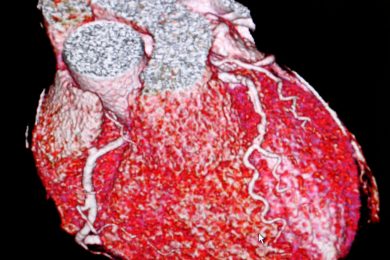

Healthy hearts initiative to tackle cardiovascular disease across region

CARDIOVASCULAR disease is responsible for one in four premature deaths in the UK, and is one of the biggest causes of death and disability¹. In West Yorkshire and Harrogate, more than 600,000 people are affected by high blood pressure (hypertension) – a…